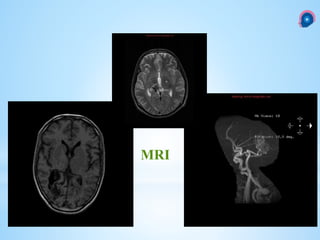

1. Flow void on T1WIor T2WIwithin the AVM

2. Feeding arteries

3. Draining veins

4. Increased intensity on partial flip-angle (to differentiate signal dropout on T1WI or T2WI

from calcium)

5. Significant edema around the lesion may indicate a tumor that has bled rather than an

AVM

6. Gradient echo sequences (GRASS) help demonstrate surrounding hemosiderin which

suggests a previous significant hemorrhage

7. A complete ring of low density (due to hemosiderin) surrounding the lesion suggests

AVM over neoplasm

MRI